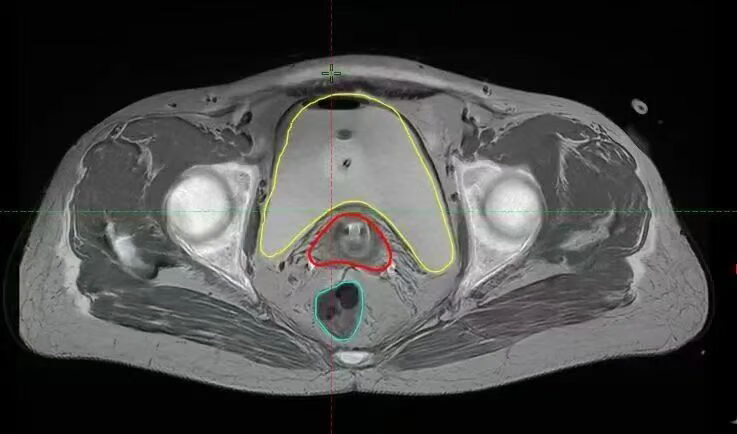

目前,大多数三维后装放疗是在CT引导下进行的,但CT在软组织显影上存在劣势,对于难治性病例,如宫旁、阴道肿瘤浸润或伴有膀胱、直肠受侵等,肿瘤往往因与正常组织器官有粘连,间隙不明显,在CT引导下难以分辨肿瘤靶区与正常组织器官的边界。MRI(核磁共振)拥有无与伦比的软组织分辨率。在定位时,它能清晰勾勒出肿瘤的三维形态、大小、浸润范围,同时能极度精准地显示膀胱、直肠、小肠等危及器官的边界。

三维后装可根据肿瘤的形态调整照射范围,在提高肿瘤照射的同时大大減低正常组织的照射。实现了靶区剂量的个体化分布,提高了靶区覆盖率,提高了患者生存率,显著降低复发率。基于高清的MRI三维图像,我们可以直接在计算机上进行三维靶区勾画和剂量学优化。物理师精确设计放射源的驻留位置和时间,让高剂量区完美包裹肿瘤(靶区),同时让危及器官的剂量曲线急剧跌落。